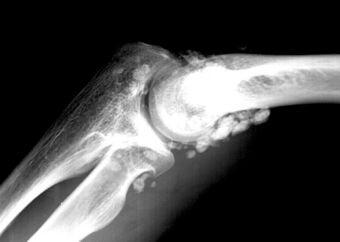

ChondromatoseCoude.jpg

X-ray of an elbow affected by synovial chondromatosis